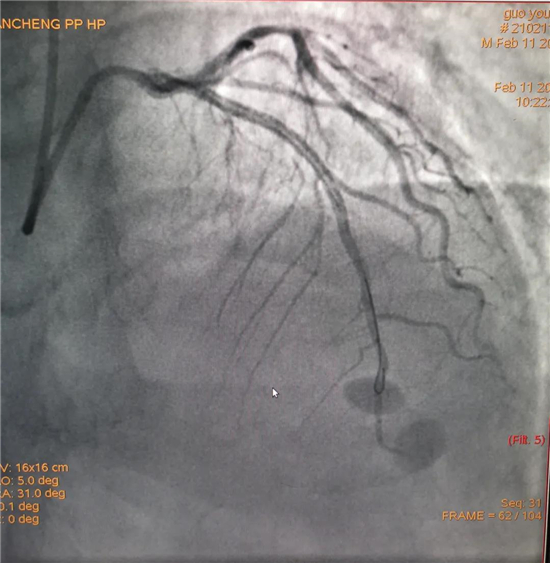

除夕,郭先生无明显诱因突发胸痛,120急救人员到达现场,心电图显示:窦性心律完全性束支传导阻滞。信息立刻发送到胸痛中心介入微信群中,心内科值班医生初步诊断为急性广泛前壁心肌梗死,必须尽快进行急诊支架治疗,开通血管。值班医生电话指导院前治疗,并立即启动胸痛绿色通道,24小时备班的介入治疗团队立即到位,9:30患者被送到导管室行冠脉介入诊疗,9:40急诊PCI手术随之开始,冠脉造影检查提示左前降支闭塞,植入支架,堵塞的血管被顺利打通,患者症状缓解,手术非常成功,10:20患者被送往病房进一步治疗。

大年初一,王女士在中午休息时无明显诱因出现上腹部疼痛,伴濒死感、大汗、剧烈呕吐,当地诊所以“胃炎”治疗无缓解,自行来我院就诊。在急诊内科快速完成心电图等相关检查后,心电图示:窦性心律,部分导联明显异常,经心内科值班医生初步诊断,该患者为急性冠脉综合征,与患者家属沟通行急诊PCI的相关事宜,沟通中了解患者高血压、2019年因急性心肌梗死在周口市中心医院性急诊冠脉介入植入1枚支架等高风险因素。风险与生命孰重,21:50 患者到导管室行急诊PCI治疗,造影提示右冠闭塞。22:18 导丝通过闭塞段,后植入支架一枚,血管再通。22:45手术结束,送往CCU观察治疗。